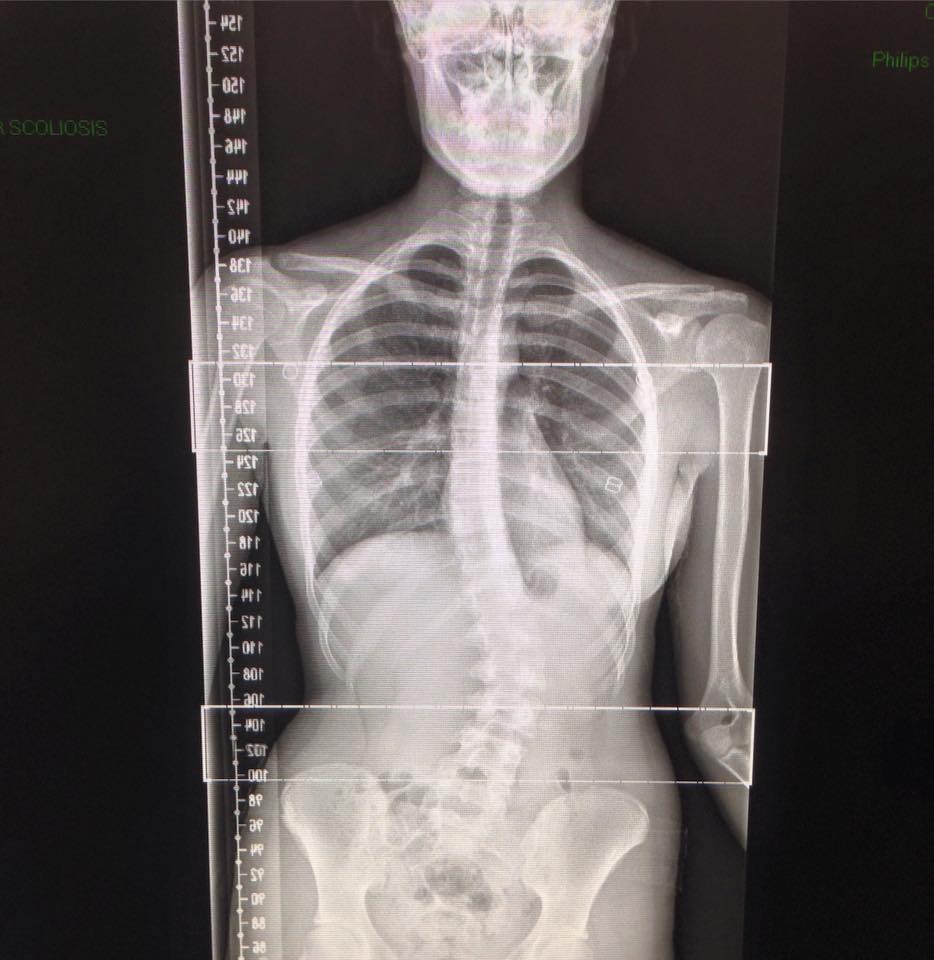

SPINE

Standing Tall